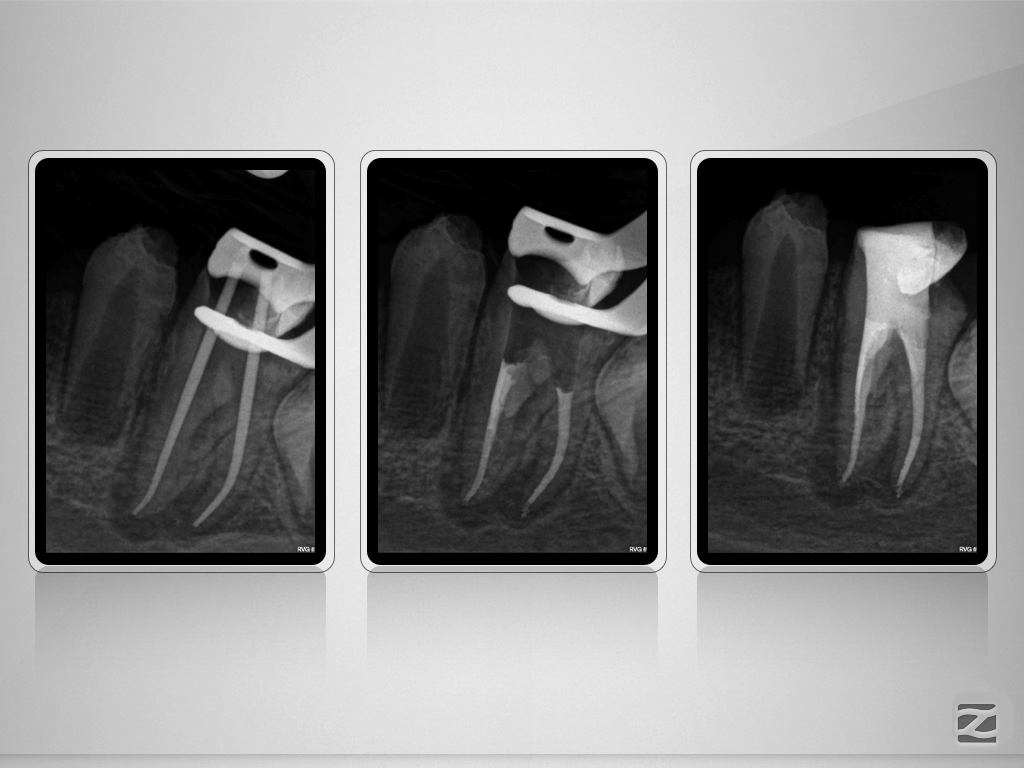

36D.009

C-shape plus Radix entomolaris